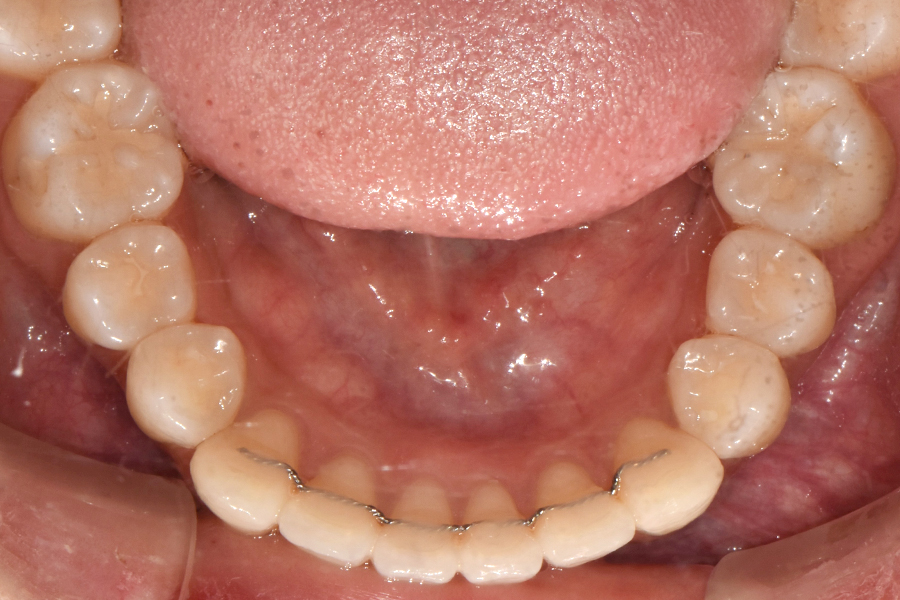

윗니를 보시면 치아 위치가 많이 틀어진 것을 볼 수 있는데요. 아래쪽 같은 경우 비교적 윗니보다 낫지만 그래도 한 쪽 치아가 좀 많이 튀어나와 있고 전체적인 악궁 형태가 조금 찌그러져 있는 것을 볼 수 있습니다.

초창기에 교정장치를 부착하고 1차 배열을 한 뒤, 대략 2개월이 지난 후의 모습입니다. 생각보다 환자분의 치아가 잘 움직여주셔서 처음보다 치아 배열이 많이 펴져 있는 것을 볼 수 있습니다.

교정을 3월에 시작하셨는데 5개월이 지난 후의 모습입니다.

부분교정의 경우에는 중심선을 맞추기가 굉장히 어려운데 환자분 교합이 괜찮으시고 치아도 잘 움직여주셔서 가운데 선을 맞출 수 있게 되었고, 교합도 거의 전체교정을 한 것처럼 아주 예쁜 효과를 얻을 수 있었습니다.

교정이 끝난 후 유지장치를 붙여드렸고 유지장치는 교정이 끝나도 최소 1~2년 정도 부착하는 것이 좋습니다.